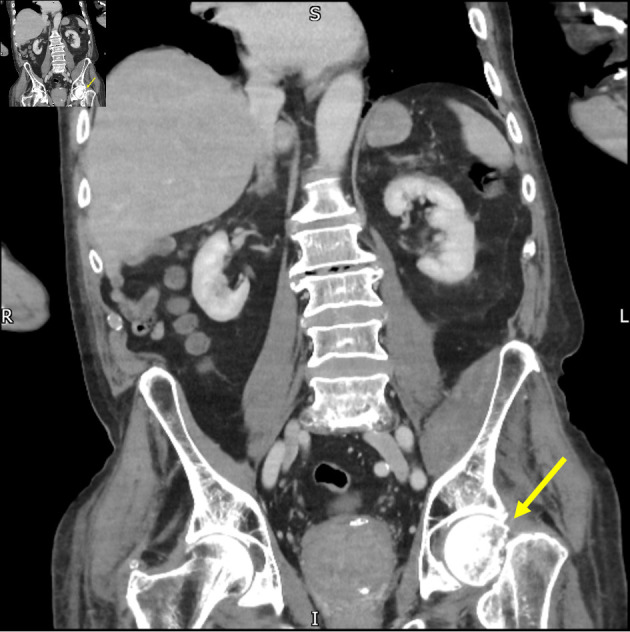

Abstract Image